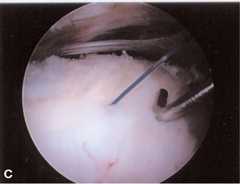

An arthroscopic technique for repair of articular surface partial-thickness tears that may promote healing by closing the tendon side-to-side, placing the debrided tendon end in contact with an abraded humeral surface is presented.